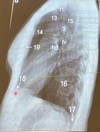

Q

•Paciente en posición recta

• Lado afectado sobre el registro

•Brazos levantados por encima de la cabeza

• Mentón hacia arriba

Posición lateral verdadera

* Rayo Central; perpendicular, dirigido a región

torácica media a nivel de 17

(8-10cms por debajo de la escotadura yugular)

¿Que proyección se desea obtener?

A

Proyección lateral